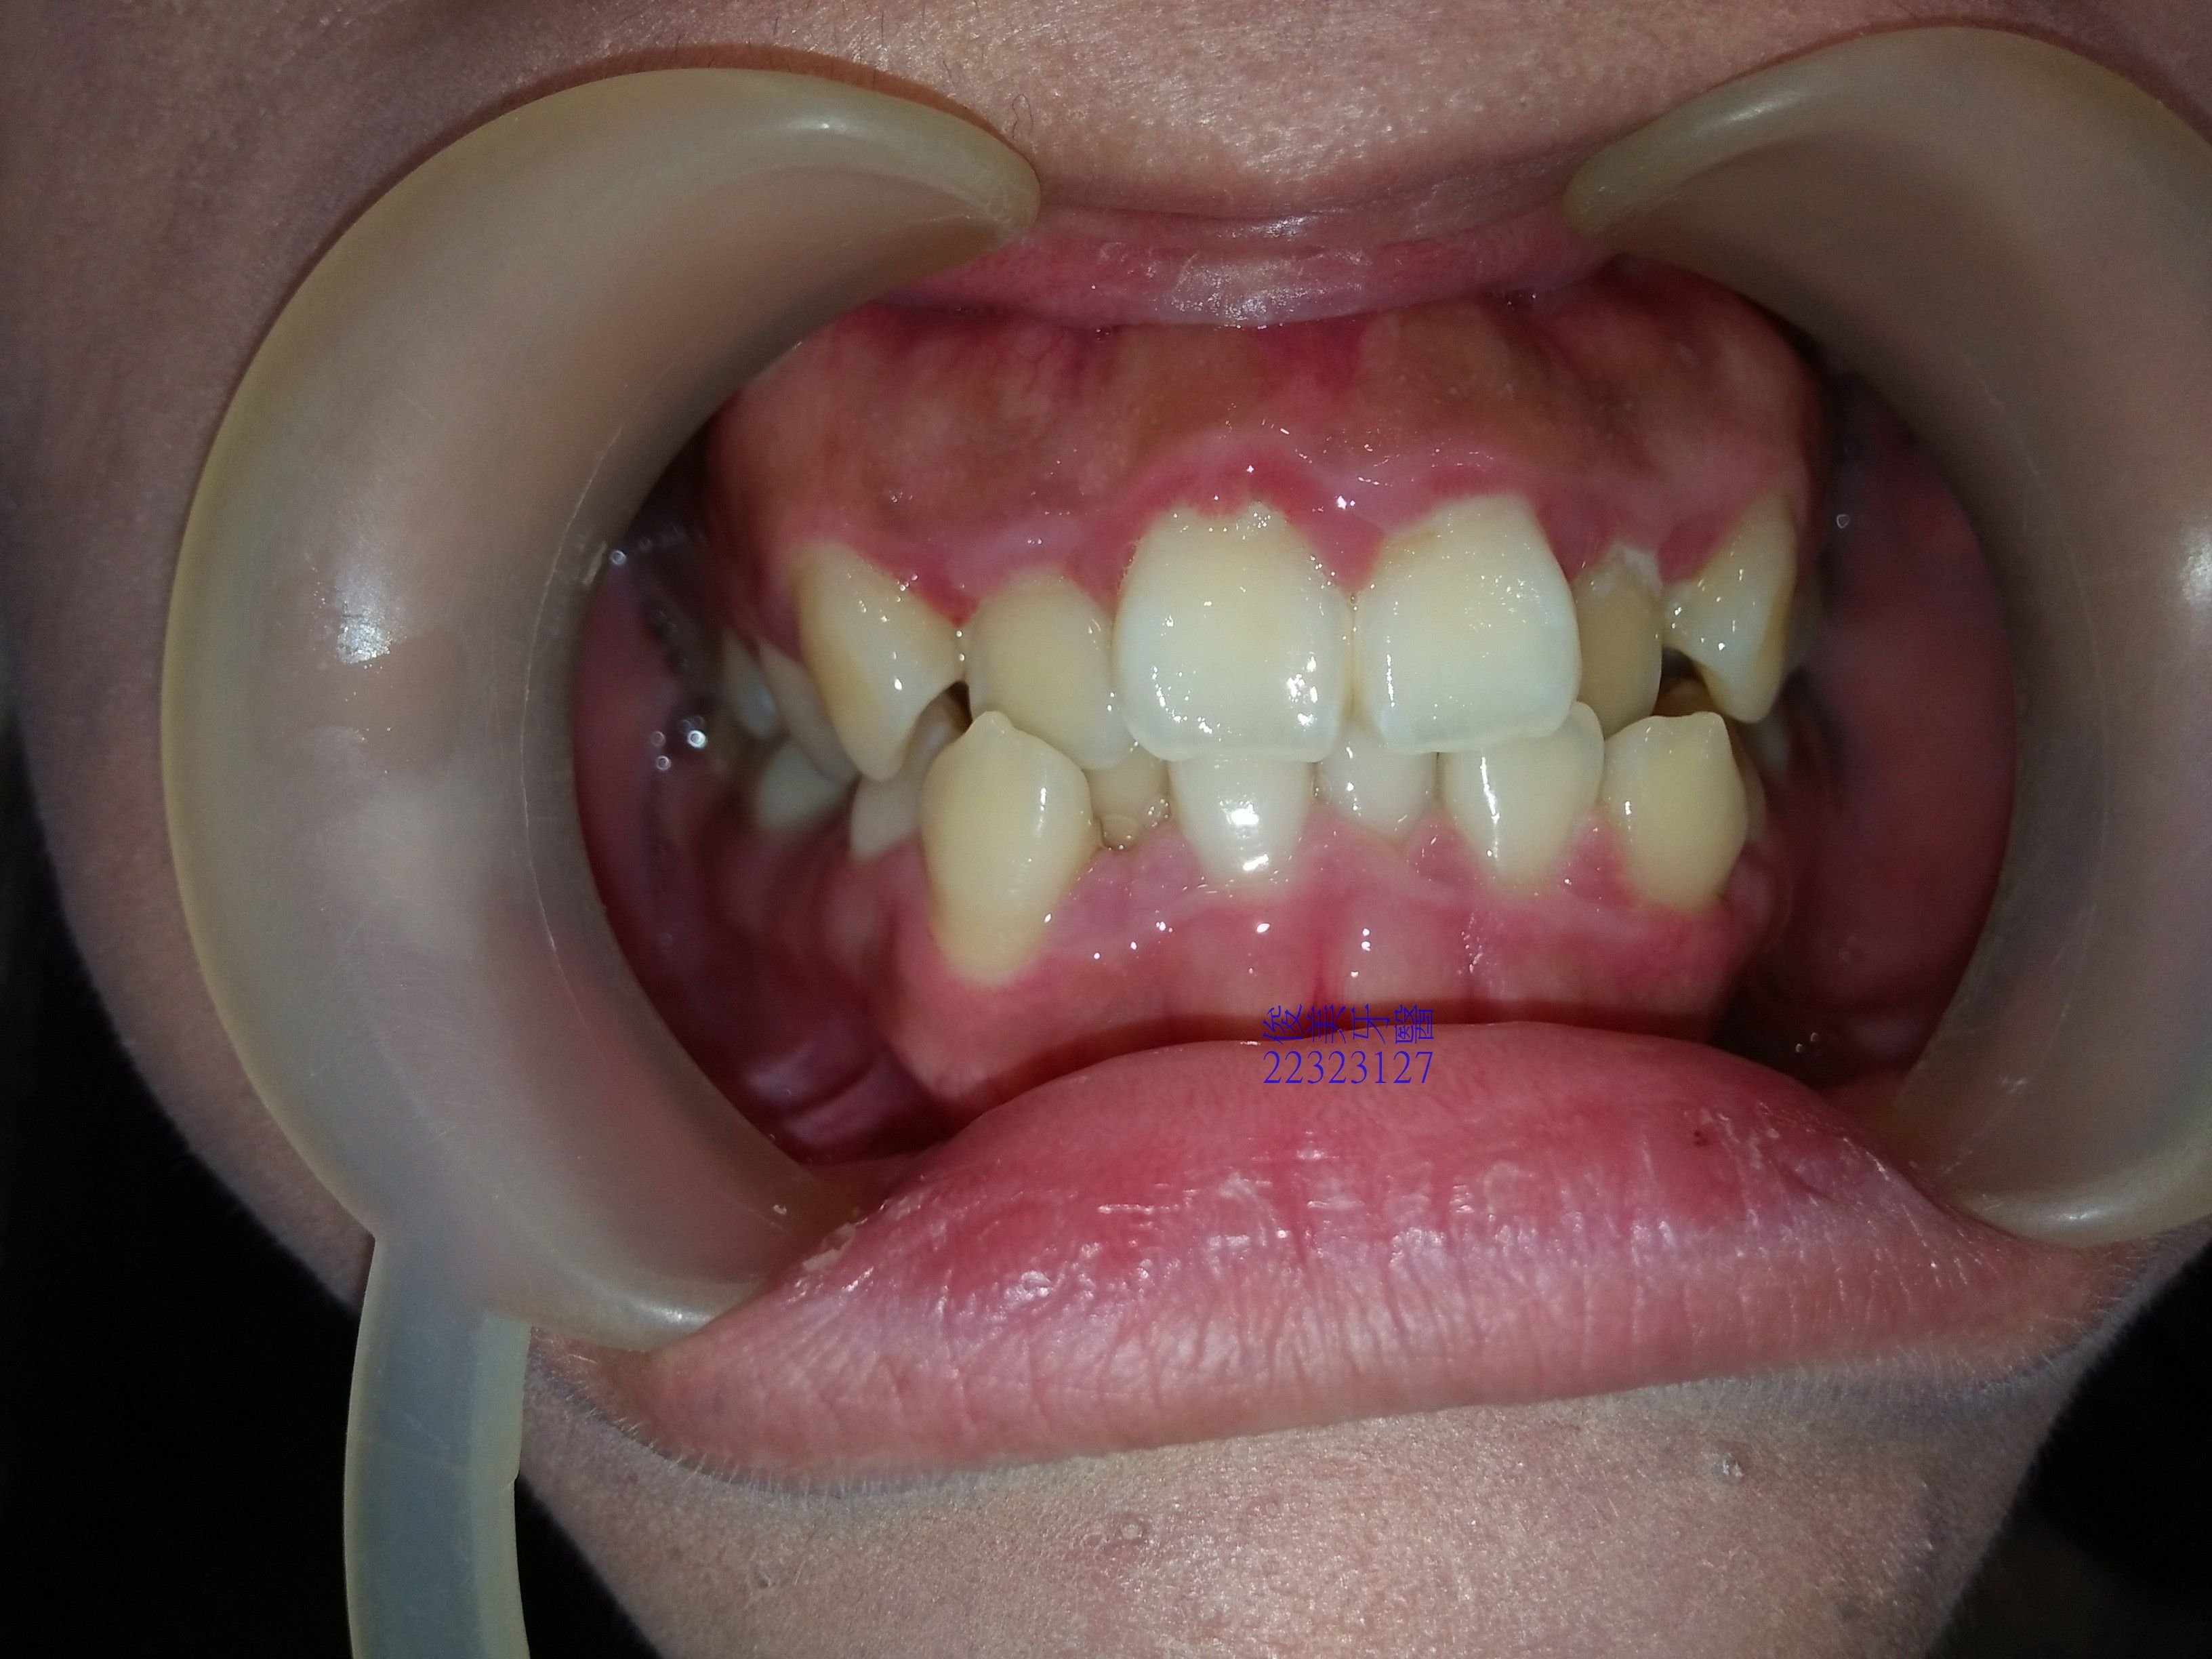

患者因牙齒排列擁擠來就診,希望能夠改善排列問題及解決牙齦長期紅腫的現象。

經醫師詳細評估後,分析問題給患者瞭解:除了排列問題存在以外,患者尚有上下顎骨架落差問題、戽斗骨架及牙齒偏小、牙齦外露.. 等,健康問題及美觀問題都有。

解決擁擠問題可以採拔除埋伏智齒釋放空間給前牙,不需拔除4顆完整的小臼齒;改善骨架落差則採榫接式人工牙冠來拉近骨架落差,不需要做正顎手術;至於牙齦紅腫起因為牙齒排列造成食物容易堆積,改善排列加上適當清潔後自然可以漸漸改善。

而微笑時牙齦外露問題及牙齒比例問題,則需靠微整型加上全瓷晶鑽貼片來改善。